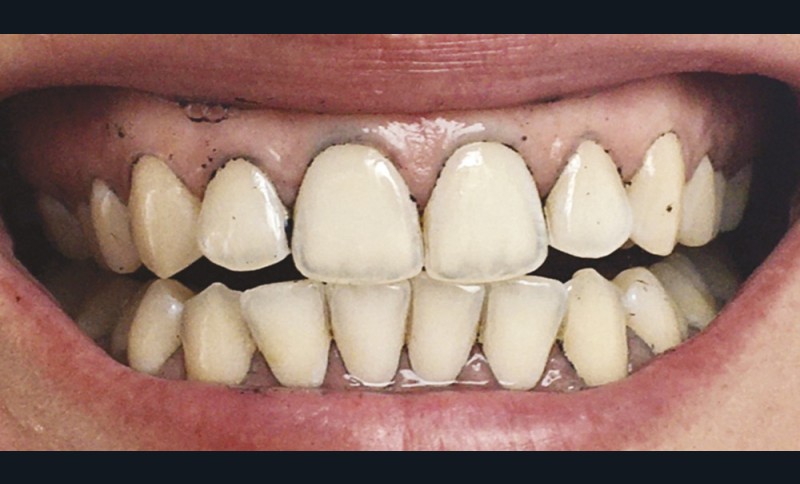

À l’heure où les ingrédients naturels sont en vogue, les produits à base de charbon végétal se sont fait une place dans les rayons cosmétiques et ceux des parapharmacies (masques, shampoings…). Et les dentifrices n’ont pas échappé à cette nouvelle tendance ! Tous ces produits vantent l’effet « blanchissant » et leurs avantages pour l’hygiène dentaire en général. Cependant, la capacité blanchissante et autres propriétés des dentifrices au charbon sont scientifiquement largement mises en doute. Au contraire, ces produits favoriseraient les caries dentaires et, à long terme, pourraient induire des effets nocifs sur les dents et les tissus parodontaux (colorations, abrasion…) [18].

Brooks et al. en 2017 [19] ont publié une revue de la littérature à partir de 118 articles et d’une base de données de cinquante dentifrices au charbon sur l’efficacité et la sûreté de ces produits. Leur première conclusion est alarmante : seulement 8 % de ces dentifrices contenaient du fluor. Et parmi ces derniers, les fluorures étaient peu ou pas efficaces pour lutter contre l’apparition de lésions carieuses. Le charbon, en raison de son fort pouvoir adsorbant, pourrait, au moins en partie, adsorber le fluor et réduire son action carioprotectrice. Les dentifrices au charbon végétal testés se voulaient « détoxifiants », « antibactériens » et « antifongiques » ; aucun de ces effets n’a pu être démontré dans la littérature, ne s’agissant que d’arguments marketing sans preuves scientifiques. 96 % des dentifrices promouvaient un effet blanchissant tout en étant peu abrasifs. Les dentifrices dits blanchissants, incluant ceux à base de charbon, possèdent uniquement un effet sur les colorations extrinsèques dues aux habitudes quotidiennes (tabac, café, thé…) par action de polissage grâce aux substances abrasives qu’ils contiennent [20]. Plus un dentifrice est abrasif, plus il est efficace pour éliminer les taches extrinsèques, mais son utilisation peut aussi engendrer des lésions d’abrasion. Le degré d’abrasivité des pâtes de dentifrice doit conserver au maximum l’intégrité des tissus dentaires tout en gardant une action nettoyante. Les fabricants doivent choisir le meilleur compromis pouvoir polissant/abrasivité.

L’abrasivité d’un dentifrice est quantifiée par l’indice relatif d’abrasion de la dentine, ou RDA (Relative Dentin Abrasivity). Cet indice renseigne sur le pouvoir abrasif d’un dentifrice en le comparant, en laboratoire, avec un témoin de référence dont l’indice est fixé à 100. Selon la norme ISO 11609, la RDA d’un dentifrice ne doit pas dépasser 250 (tableau 1). Entre 70 et 100, il est considéré comme moyennement abrasif, et dangereux pour la dentine et le cément. La réglementation en vigueur n’oblige pas les fabricants à mentionner la RDA sur les emballages des dentifrices. 96 % des dentifrices testés dans l’étude de Brooks et al. vantaient un effet peu abrasif, or un seul possédait un indice RDA faible [20].

Lors du brossage avec un dentifrice ou une poudre à base de charbon actif, il se crée une mousse gris noire, parfois difficile à éliminer. Des particules noires se déposent, et s’accumulent dans les sillons et anfractuosités des dents, au niveau des zones de jonctions des restaurations et au niveau de la gencive, laissant ainsi un liseré noir inesthétique (fig. 6). Pour supprimer ces colorations, un brossage plus long, plus actif, voire répétitif est souvent nécessaire (fig. 7 et 8).

Ainsi, en recherchant l’effet blanchissant, les utilisateurs de ces produits auraient également tendance à multiplier le nombre de brossages quotidien. Par conséquent, les lésions d’abrasion pourraient apparaître plus rapidement et/ou être accentuées. En effet, l’abrasivité ne dépend pas uniquement de l’agent abrasif, mais également de la technique et du nombre de brossages, de la dureté des poils de la brosse à dents, et de la fréquence d’utilisation des dentifrices dits « blanchissants ».